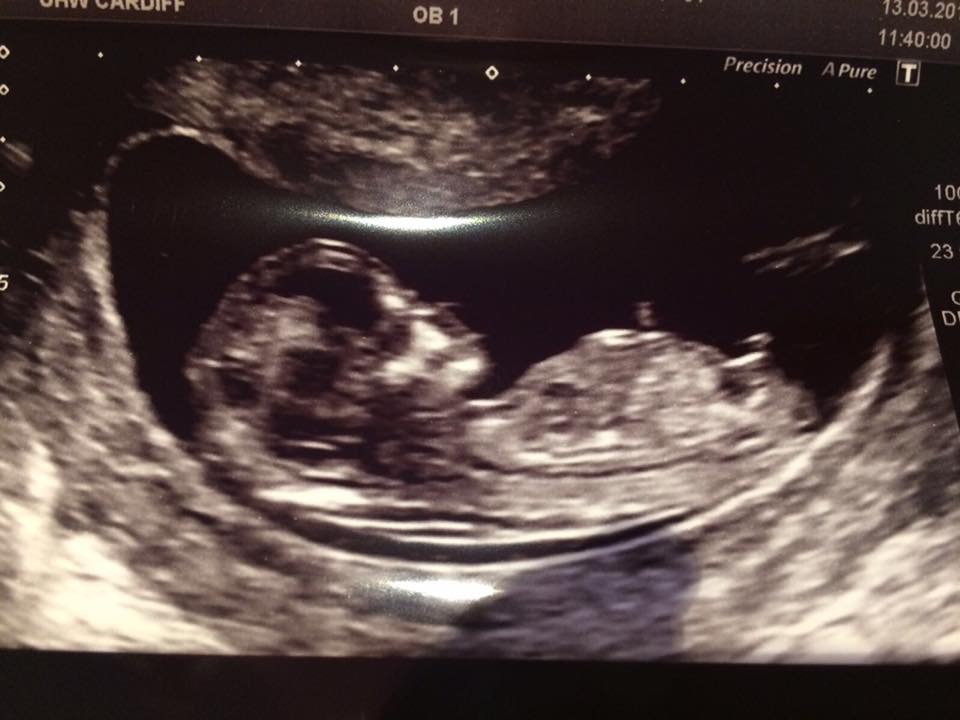

Can you please let me know if you think boy or girl?Attachment 35377Attachment 35379Attachment 35380

I thought the nub looked horizontal to the spine as baby is curved. Was thinking girl but everyone else thinks boy so guess I'm missing something xx

Definite boy, it's all about the stacking!x

Definitely boy! It's the bump above the nub = boy for sure!

The nub is short, angled upward, with stacking above the nub. This is a very classic boy nub. Congrats [emoji170]!